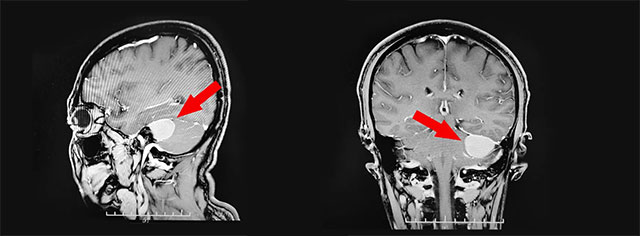

▲ 腫瘤位于左側(cè)橋小腦角區(qū)

頭顱MRI平掃+增強顯示:左側(cè)橋小腦角區(qū)可見團塊狀異常信號,形態(tài)不規(guī)則,毗鄰左側(cè)小腦半球可見受壓。神經(jīng)外科6B病區(qū)李士其教授分析指出,根據(jù)影像考慮為小腦腦橋角腦膜瘤。由于腫瘤較大,位于顱腦底部,位置較深,且與“生命中樞”腦干毗鄰,周圍相關(guān)顱神經(jīng)有9條,有非常重要的小腦前下、后下動脈,腫瘤血運豐富,手術(shù)難度極大,稍有不慎將帶來巨大風險及嚴重的手術(shù)并發(fā)癥,甚至危及生命!